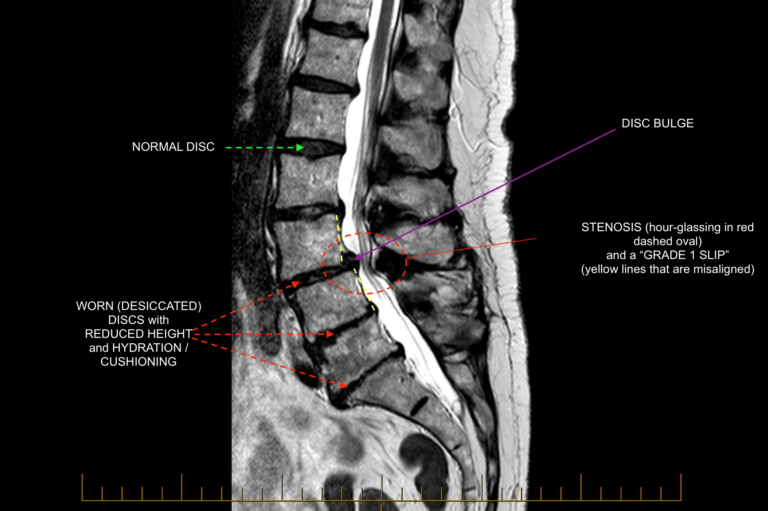

Normal Versus Abnormal Lumbar Anatomy C N S Neurosurgery

https://www.cnsneurosurgery.com.au/wp-content/uploads/2020/09/3.-Abnormal-lumbar-T2-sagittal-768x511.png

Lumbar Spine MRI Mri Scan Images Sciatica Treatment Disk

https://i.pinimg.com/originals/76/7e/c8/767ec8b4e44bb129b3d740de50bb7a0f.jpg